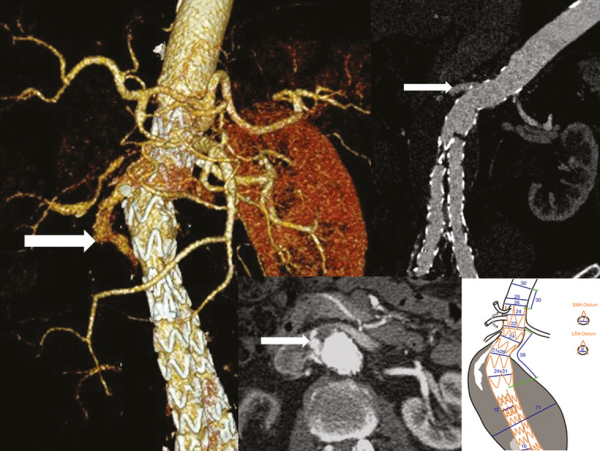

Abbildung 1: Produkt: E-ventus® Vertrieb: Jotec GmbH 3D-Rekonstruktion eines Follow-up-CT-Scans, das 4 Jahre nach dem Ersteingriff aufgenommen wurde, zeigt den Verlust der proximalen Abdichtung und das Endoleak vom Typ Ia (A). Eine gecurvte multiplanare 2D-Rekonstruktion (B) und eine axiale Ansicht zeigt das Kontrastmittel innerhalb des Aneurysmas und außerhalb des Stentgrafts (C). Der Stentgraft befand sich in derselben Position, in der er während des Ersteingriffs eingesetzt wurde, was darauf schließen lässt, dass die fortschreitende Halsdilatation die Ursache war. Mit einem präoperativen CT-Scan mit 1-mm-Schichten wurde eine Skizze von Jotecs E-xtra DESIGN ENGINEERING (D) erstellt. Diese Skizze wurde dann vor der Vorbereitung der technischen Zeichnung mit den behandelnden Ärzten besprochen. |

Vertrieb: Jotec GmbH 3D-Rekonstruktion eines Follow-up-CT-Scans, das 4 Jahre nach dem Ersteingriff aufgenommen wurde, zeigt den Verlust der proximalen Abdichtung und das Endoleak vom Typ Ia (A). Eine gecurvte multiplanare 2D-Rekonstruktion (B) und eine axiale Ansicht zeigt das Kontrastmittel innerhalb des Aneurysmas und außerhalb des Stentgrafts (C). Der Stentgraft befand sich in derselben Position, in der er während des Ersteingriffs eingesetzt wurde, was darauf schließen lässt, dass die fortschreitende Halsdilatation die Ursache war. Mit einem präoperativen CT-Scan mit 1-mm-Schichten wurde eine Skizze von Jotecs E-xtra DESIGN ENGINEERING (D) erstellt. Diese Skizze wurde dann vor der Vorbereitung der technischen Zeichnung mit den behandelnden Ärzten besprochen. |